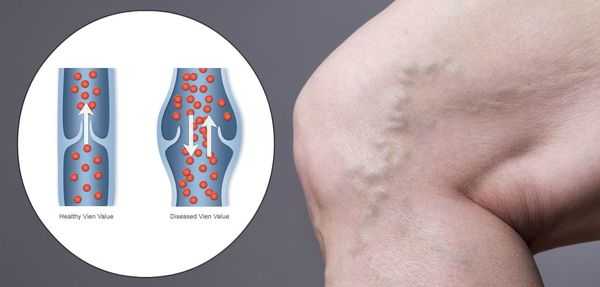

Патогенез ХВН очень специфичен. У здорового человека отток крови происходит через глубокие вены голени. Благодаря совместной работе постоянно сокращающейся и расслабляющейся скелетной мускулатуры и клапанного аппарата кровь направляется к сердцу, где она насыщается кислородом. В процессе этой работы гладкая скелетная мускулатура усиливает давление на вены, а клапанная система, которая состоит из смыкающихся створок, не позволяет крови поддастся силе тяжести.

Из-за длительно существующих факторов риска возникает венозная гипертензия, происходит расширение и выпячивание стенки вен. Створки клапанов расходятся и не могут препятствовать патологическому оттоку крови. Увеличенный объём крови сильнее давит на стенку вены, поэтому вена расширяется. Если не начать лечение, вена продолжит расширяться. Стенки сосудов начнут стремительно терять свою эластичность, их проницаемость увеличится. Через стенки в окружающие ткани будут выходить элементы крови, плазма. Таким образом возникает отёк тканей, что еще больше обедняет их кислородом. В тканях накапливаются свободные радикалы, медиаторы воспаления, запускается механизм активации лейкоцитов. Это нарушает питание и обмен веществ тканей. Конечным итогом становится образование «венозных» трофических язв, что существенно снижает качество жизни пациента. [4] [6]